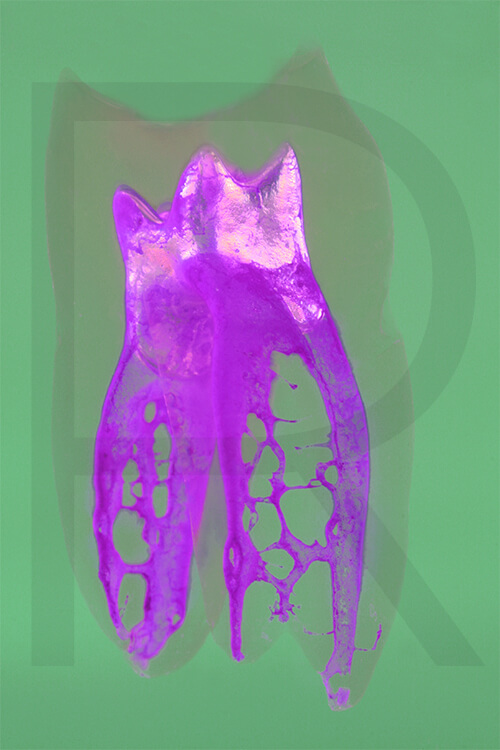

Bildauswahl Pop Art

- Foto hinter 3mm Acrylglas, rahmenlos

- hochwertige, unsichtbare Aufhängung, "schwebend“

- Hoher UV-Schutz für lang anhaltend strahlende Farben

- Bruchsicher und leichter als Glas

- Beeindruckende Farben und brilliante Tiefenwirkung

- Druck erfolgt ohne Wasserzeichen

- Bildgröße Variante 1: 90 x 120 cm

- Preis auf Anfrage, zuzüglich 20,90 Euro Versand & Porto innerhalb Deutschlands, weiterer Versand auf Anfrage

- Bildgröße Variante 2: 90 x 90 cm, quadratisch

- Preis auf Anfrage, zuzüglich 20,90 Euro Versand & Porto innerhalb Deutschlands, weiterer Versand auf Anfrage

- Bildgröße Variante 3: 60 x 120 cm, Hochformat

-

Preis auf Anfrage, zuzüglich 20,90 Euro Versand & Porto innerhalb Deutschlands, weiterer Versand auf Anfrage

Wenn Sie Interesse an den Fotos transparenter Zahnpräparate haben, bieten wir hier die Möglichkeit einige Versionen als Acrylbilder (alle Detailinformationen zu Größe und Preis siehe obige Auswahl) zu bestellen.

Die Bilder sind nicht nur zur Praxisverschönerung geeignet sondern auch eine wertvolle Unterstützung bei der Patientenberatung vor endodontischen Behandlungen.